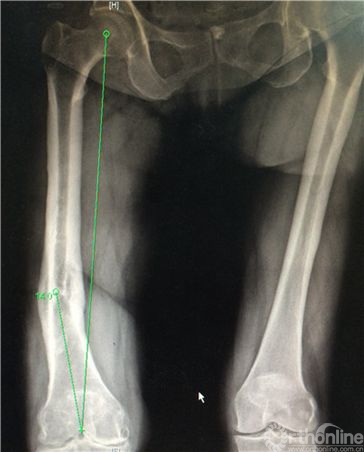

(2)畸形发生在冠状位,关节外股骨中下段;下肢全长片测量,股骨中下段内侧成角,股骨外翻角约14度(图1b);

图1b. 右股骨中下段内侧成角畸形,股骨外翻角约14度。